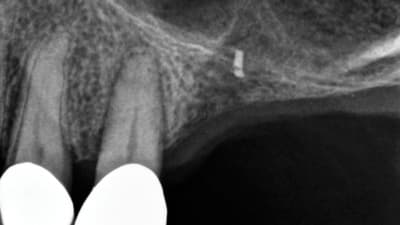

Special Report General Dentistry Digital Imaging Digital Radiography in General Practice: Is It Time to Convert? By Claudio M. Levato, DDS August 01, 2013 9 min read

Special Report Carestream Dental: Innovative Imaging Solutions Benefiting Patients and Practices August 01, 2013 4 min read

Special Report XDR Radiology: Digital Solutions Designed by Dentists for Dentists August 01, 2013 4 min read